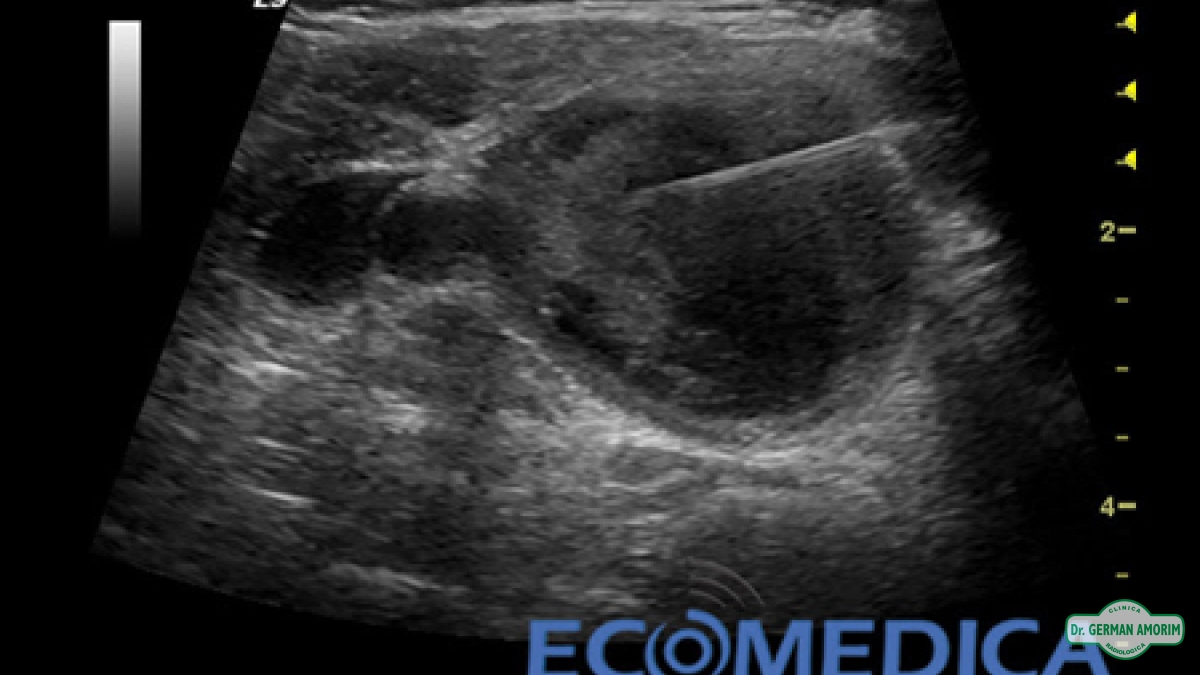

Consiste en una punción ecodirigida y sirve para obtener células de un área específica del cuerpo para su análisis citopatológico y de esta forma definir si se trata de un contenido maligno o benigno.

En el caso de ser un quiste nos permite vaciarlo y enviar ese contenido al patólogo.